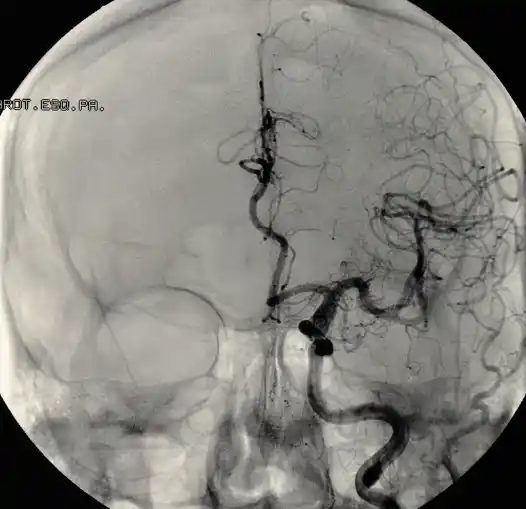

뇌경색 치료 방법 2. 혈관 내 시술

혈관이 막힌 지 4시간 이상인 경우, 혈관 내 시술을 시행할 수 있습니다. 혈관 내 시술은 카테터를 이용하여 혈관을 막고 있는 혈전을 제거하거나, 혈관을 확장하는 치료 방법입니다.